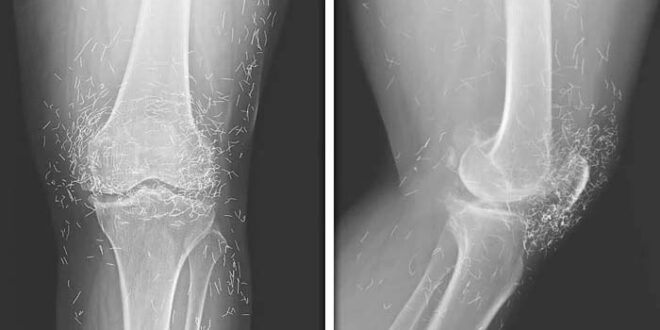

ڈاکٹرز کو خاتون کے گھٹنوں کے ایکس رے میں سونے کے چھوٹے چھوٹے سیکڑوں دھاگے بھی نظر آئے جو کہ ایکیوپنکچر کرتے ہوئے گھٹنوں میں ڈالے گئے تھے۔

ڈاکٹروں کو معلوم ہوا کہ یہ دھاگے عورت کے ایکیوپنکچر علاج کے حصے کے طور پر ڈالے گئے تھے۔